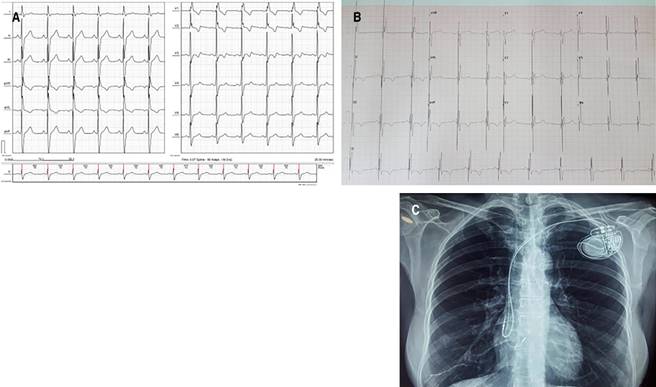

The procedure was performed without complications. The His-bundle stimulation threshold was 1 V with a pulse width of 0.6 in unipolar stimulation. The impedance was 232 Ohms, and the R wave amplitude was 3.3 mV. The baseline QRS measured 160 ms, and after His stimulation, it shortened to 100 ms. Figure 1 shows the baseline ECG as well as the ECG and chest X-ray control prior to discharge the day after PM implantation. The stimulated AV delay was set to 180 ms and the sensed one to 160 ms. Since then, the patient has not presented any new syncope events.

Figure 1: In the first panel (A) is the baseline electrocardiogram (ECG) of the patient with sinus rhythm, right bundle branch block, and 1:1 atrio-ventricular (AV) conduction. B) Shows the predischarge control ECG with unipolar stimulation and His capture, with normal intraventricular conduction (narrow QRS), and the chest film (C) showing the position of both electrodes prior to discharge. Note that the His electrode was located in the interatrial septum.